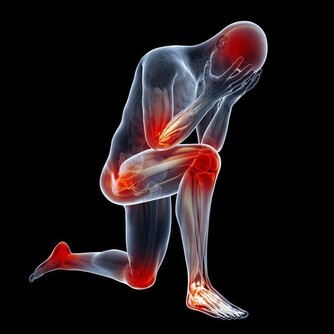

TOP1爬樓梯

相關數據顯示,在60歲以上的老人跌倒中,

超過51%與爬樓梯相關,爬樓梯每年導致2萬人死亡。

進入老年後,人體肌肉會減少3%-5%,關節開始退化,上下樓梯或者爬山時,

膝關節承受人體重量是平時的3-5倍,這會加重關節老化。